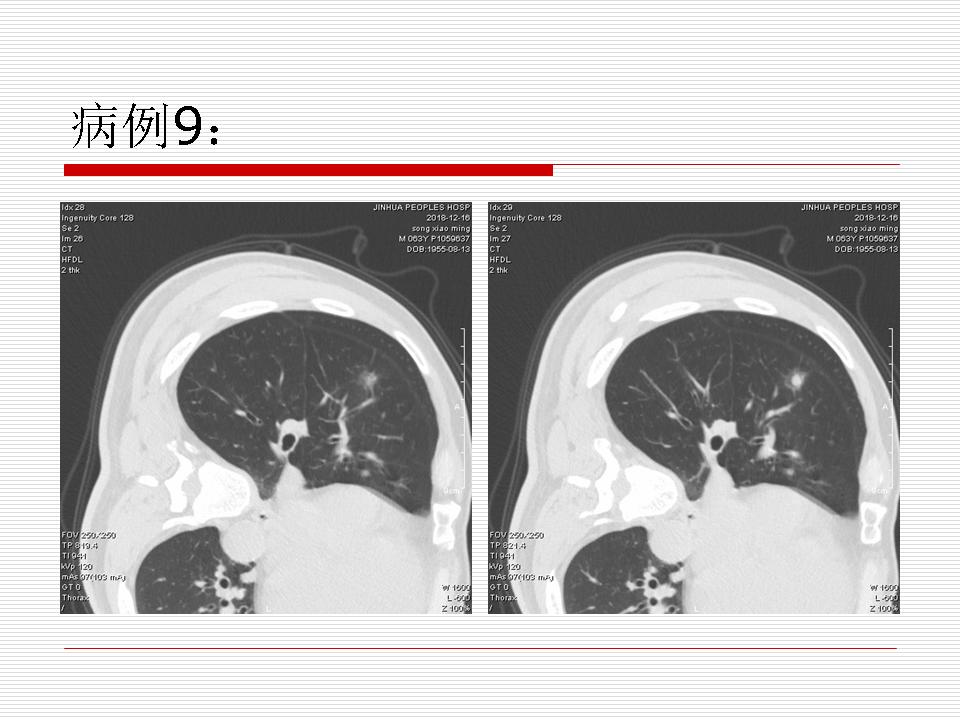

肺部阴影永恒且最重需要鉴别的是:到底是炎症还是肿瘤?但临床的病例中的影像表现难以界定或有些肿瘤特征,同时又有些炎症特点是非常常见的情况。作为临床医生我们怎么去总结分析,并找到之所以是炎症或之所以是肿瘤的细微差别或特点非常重要,也非常有用。2019.12.7浙江省2019年胸心外科学学术年会在宁波召开时,我的临床病例分析与经验总结<那些像肺癌的炎症与像炎症的肺癌>获得在大会交流的机会,以下为该PPT的内容,与你分享,希望对同道有益,有借鉴与启迪。若有探讨与进一不完善的建议,欢迎文末留言讨论: